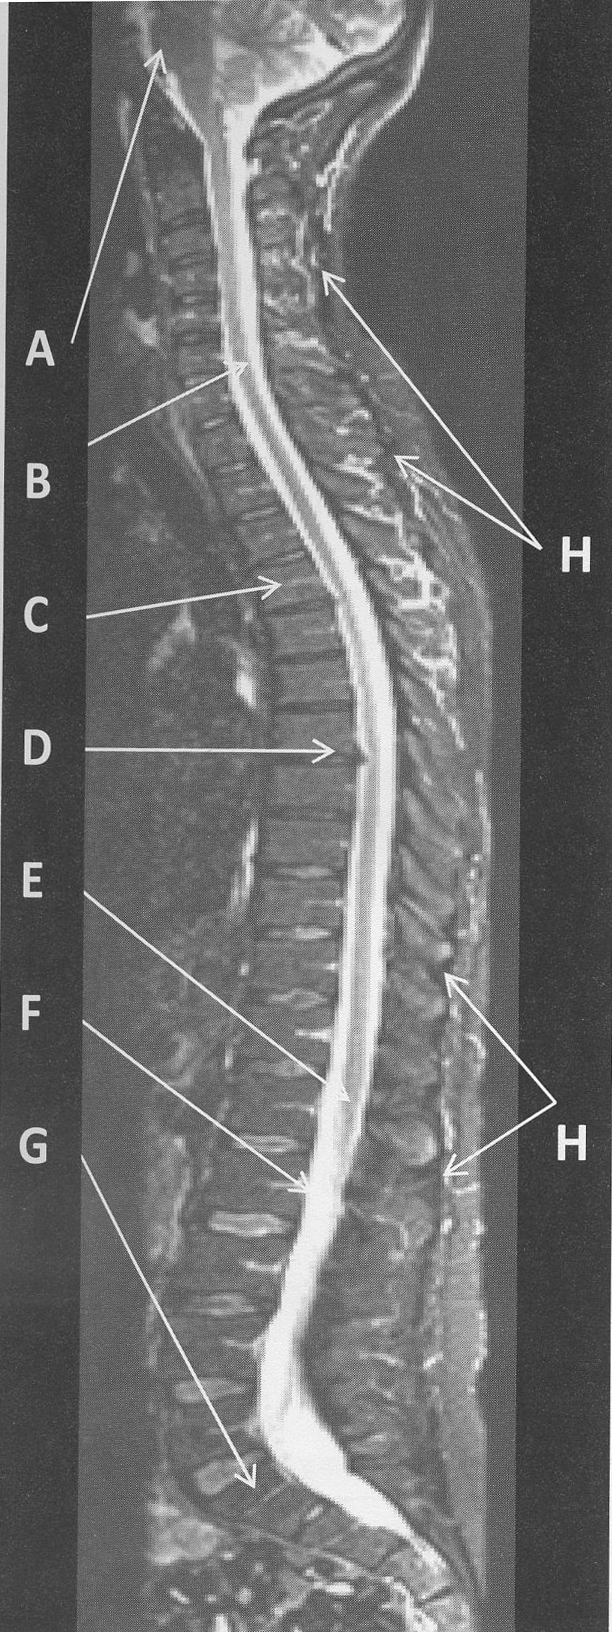

figure B 11 was acquired with a 48cm rectangular FOV, 4 mm slice thickness, and a 512x512 matrix. A small FOV image that would bear the same spatial resolution is

24 cm FOV, 4 mm slice thickness and 256x256 matrix

judging from the SNR on figure B 11 the coil or coils that were most likely used to acquire this image are

phased array

figure B 11 the low signal intensity area (arrows H) that runs superior and inferior but posterior to the spinous process represents

spinatus tendon

figure B 11 was acquired in the ______plane

sagittal